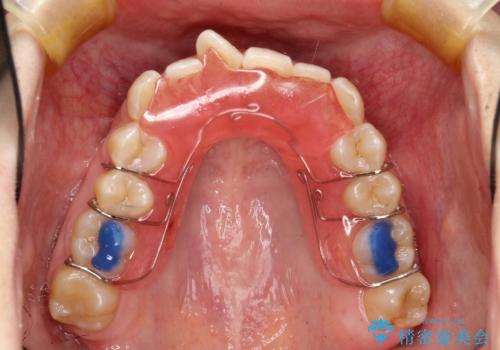

- 矯正装置

- 審美装置

- 非抜歯、大臼歯遠心移動による臼歯関係の是正・過蓋の改善をハーフリンガル・ワイヤー矯正にて計画した。

しかし、諸々の理由でマウスピース矯正をおこなえない場合、本例のようにワイヤーを用いて治療することも可能ですが、そもそも装置が歯につかないため、非常に大変な労力を費やすことになります。